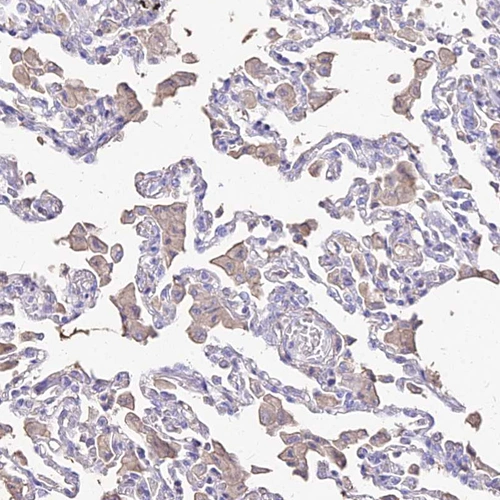

Immunohistochemical staining of human fallopian tube shows strong positivity in cilia of glandular cells.